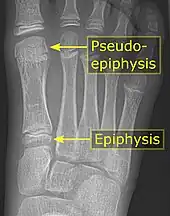

Pseudo-epiphysis

It is common in children to have a pseudo-epiphysis of the first metatarsal.[10]

A pseudo-epiphysis is an epiphysis-looking end of a bone where an epiphysis is not normally located.[11] A pseudo-epiphysis is delineated by a transverse notch, looking similar to a growth plate.[11] However, these transverse notches lack the typical cell columns found in normal growth plates, and do not contribute significantly to longitudinal bone growth.[12] Pseudo-epiphyses are found at the distal end of the first metacarpal bone in 80% of the normal population, and at the proximal end of the second metacarpal in 60%.[11]